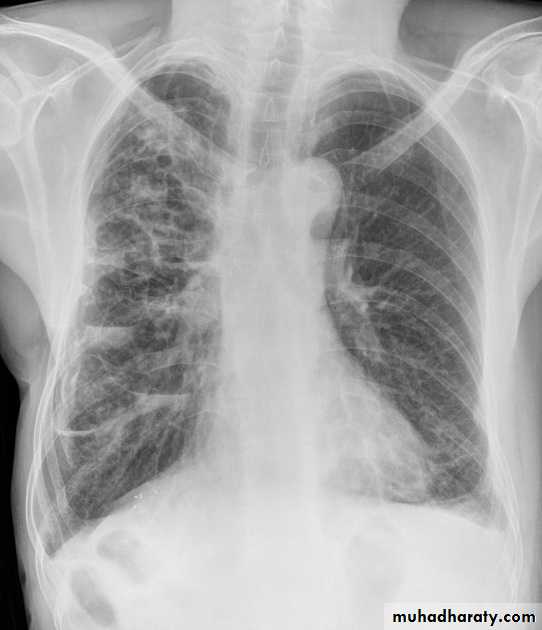

Plain radiograph

Chest x-rays are usually abnormal

1. Tram-track opacities are seen in cylindrical bronchiectasis, and

2. air-fluid levels may be seen in cystic bronchiectasis.

Honey comb shadow

3.Overall there appears to be an increase in bronchovascular markings, and bronchi seen end on may appear as ring shadows .

4.Pulmonary vasculature appears ill-defined, thought to represent peri bronchovascular fibrosis .